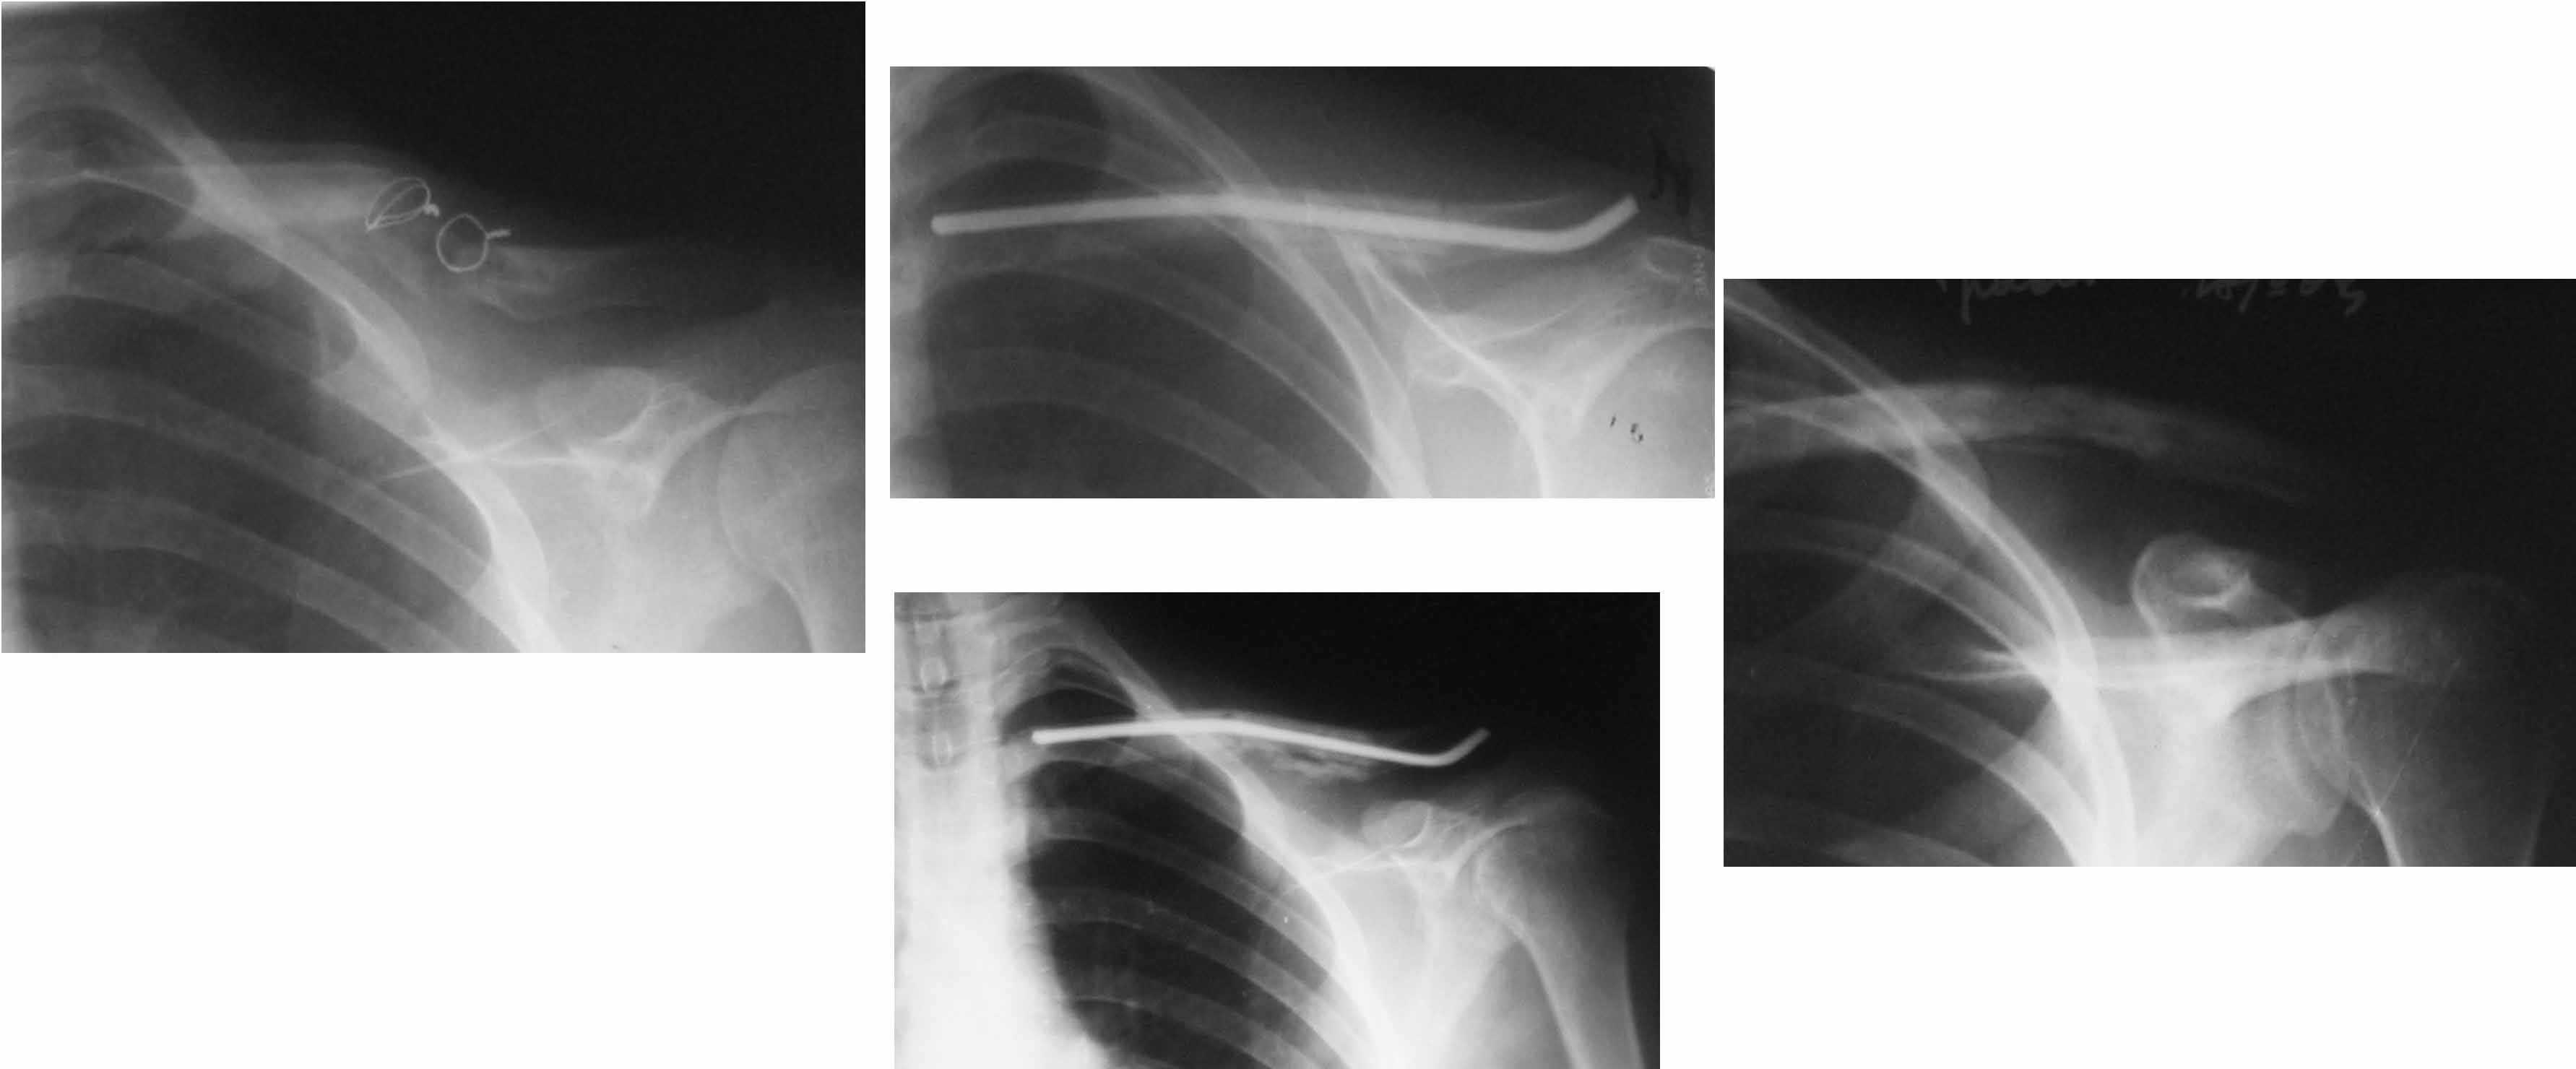

Идеальным вариантом представляется резекция ложного сустава, замещение образовашегося дефекта васкуляризированным малоберцовым трансплантатом и интрамедуллярный блокированный остеосинтез.

В условиях российской бедности мы делали свободным "столбиком" из малоберцовой и неблокированным штифтом. Результат был хороший (фото).